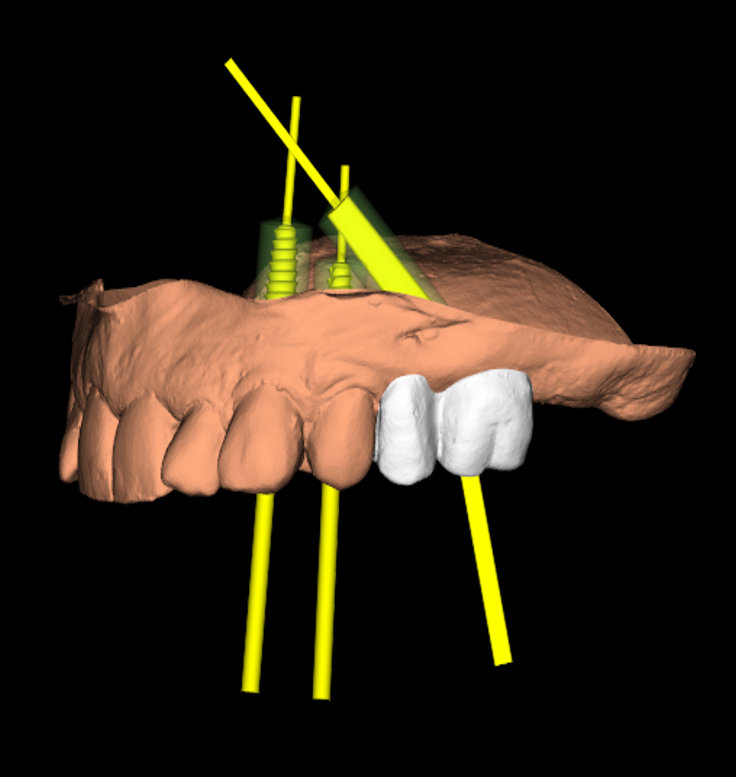

For moderate to severe maxillary atrophy, in the presence of surgically challenging sinus anatomy, the apex of the posterior implants can be angled anteriorly, passing transsinus, to apically fix at the lateral piriform rim into the lateral nasal wall. The most important bone for apical fixation of implants in this setting is the lateral nasal bone mass with the maximum available bone found at the piriform rim above the nasal fossa (4,5). This area, designated the M point, also can engage two implants placed at 30-degree angles (Figs. 1a-b). The transsinus implants are then grafted and possibly placed into immediate function, depending on the level of crestal stability present.

Digital implant project: three different views of the same procedures.